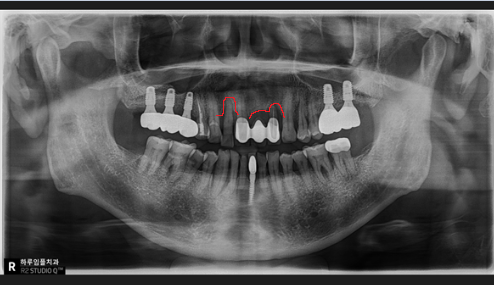

저희 하루임플치과에서는 3D CT를 통해 골밀도와 잔존 골량을 입체적으로 분석합니다.

0.1mm의 뼈 두께까지 계산하여 가장 효율적인 이식 범위를 결정하므로, 불필요한 과잉 수술 없이도 튼튼한 기초를 다질 수 있습니다.